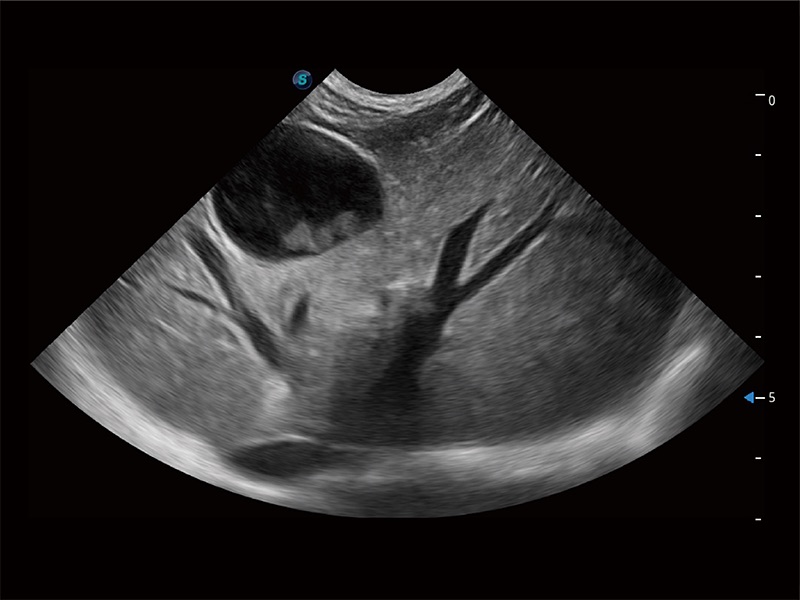

ProPet 80 配備了豐富的心臟探頭群、先進(jìn)的成像技術(shù)和專業(yè)的心臟測量工具,可幫助動物醫(yī)生為不同體型和生理結(jié)構(gòu)的動物提供心臟和心肌功能的全面評估。

ProPet 80 全新的動物超聲智能軟件和豐富的探頭群,為動物醫(yī)生提供了高清晰度和精細(xì)分辨率的圖像,無論在寵物、馬科、畜牧還是實驗室動物等應(yīng)用中都可以輕松應(yīng)對,為您的日常工作帶來滿意的體驗。